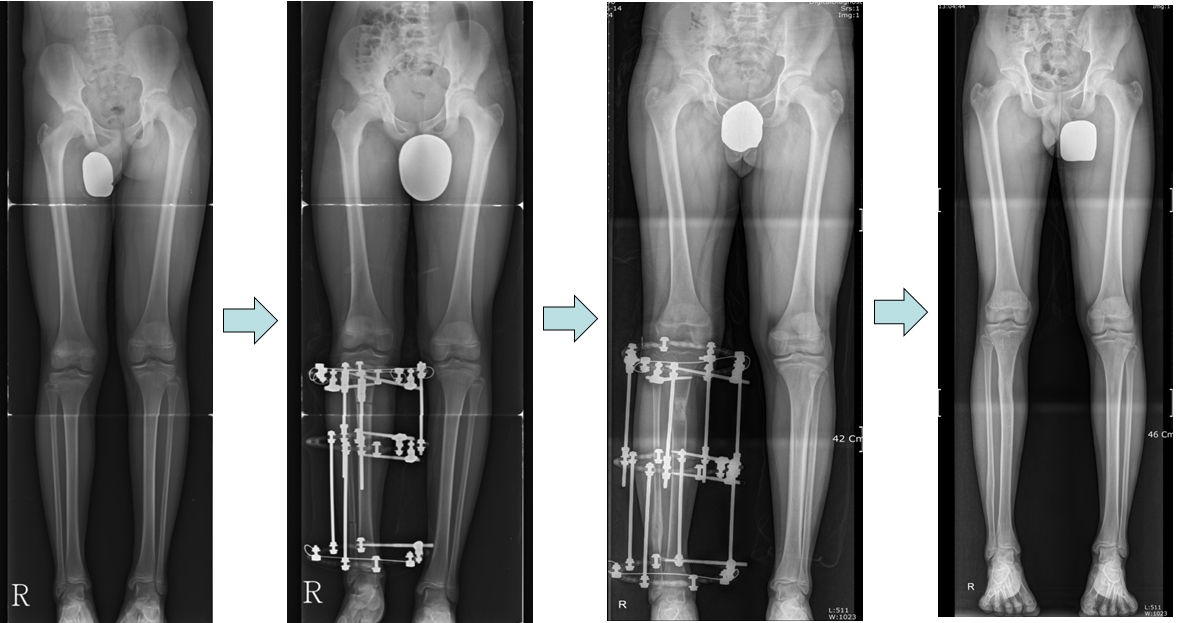

공지 한쪽다리 짧은 환자에서 종아리뼈 연장관리자2025-09-25 20:29오른쪽다리의 종아리뼈부분이 짧은상태로 연장후 두다리 길이가 같아진 모습입니다. Right tibia was shorter than the other. Lengths of two legs became same after lengthening. 다음글공지 발가락짧은 환자에서의 연장술이전글공지 한쪽다리 짧은환자에서 허벅지뼈 및 종아리뼈 연장목록